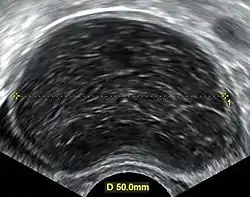

| A simple ovarian cyst of most likely follicular origin | |